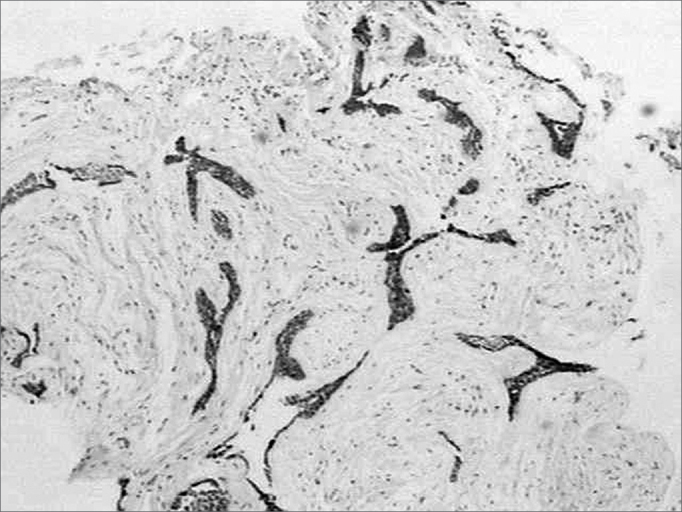

The histopathology exam showed areas of desmoplastic and follicular ameloblastoma. In the former we observed tumoral epithelial islets spread in a densely collagenized connective stroma (Figure 1). These tumoral islets, which seemed to be compressed, were made up of cuboid or spindle-shaped cells showing cellular periphery in palisade absent. The second histology subtype was represented by epithelial islets of which peripheral cells were distributed in palisade, similar to the ameloblastomas of the enamel organ (Figure 1). The cells in the central region were similar to the stellar reticulum of the enamel organ. Often times these cell arrangements showed cystic degeneration and, eventually, squamous metaplasia. The stroma was less dense and made up of scarce lymphocytes.

Figure 1.

Connective stroma densely collagenized and permeated by compressed epithelial neoplastic islets, as well as by epithelial islet with peripheral cells arranged in palisade (H/E, 40x).